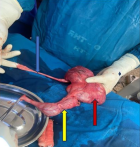

Therapeutic intervention: an emergency nephrostomy tube was passed to the right kidney, which drained about 7 L of clear urine. The parents were then counselled for the right nephroureterectomy on account of severe hydronephrosis and a dysplastic kidney. The patient was draped and prepped under general anaesthesia, an extended midline incision was made at laparotomy, and the following findings, as seen in Figure 4, were made: 1. Lower moiety ureter insertion in the bladder with moderate dilatation consistent with vesicoureteric reflux with reflux nephropathy. 2. Upper moiety ectopic ureter insertion in the adrenal gland. The right testis was seen in the pelvis, exploration of the testis was done, and the testis was seen to be viable; right orchidopexy was done.

Figure 4: kidney showing ureteral duplication with the upper moiety ureter, which was inserted into the adrenal gland; the red arrow shows the kidney, the yellow arrow shows the dilated lower moiety ureter, and the blue shows the upper moiety ureter that is inserted into the adrenal gland (adrenal gland not shown)